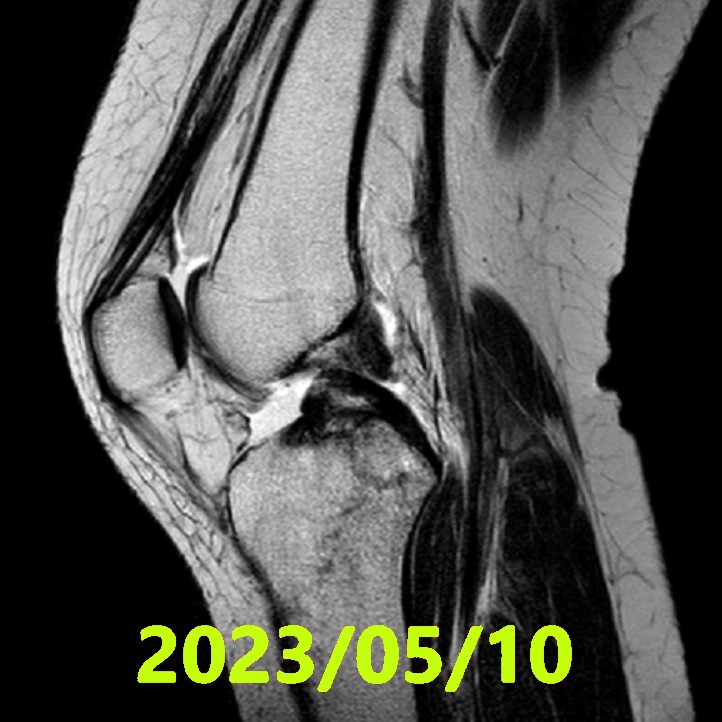

初期評估(MRI ①)

- 拍攝日期:2023 年 5 月 10 日

- 影像診斷:委託 3 名獨立影像專家。若意見分歧,則透過合議制得出最終診斷。

- Ihara 分類:合議結果判定為 Ⅳ 型(Type 4)(斷端模糊的最嚴重完全斷裂)